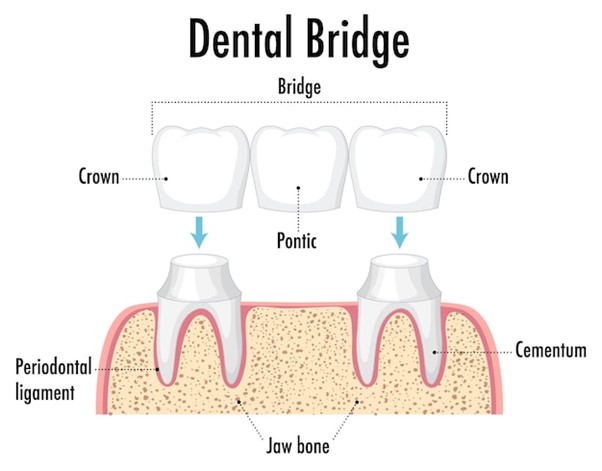

Dental bridges are a type of dental restoration used to replace one or more missing teeth. They are typically made up of one or more